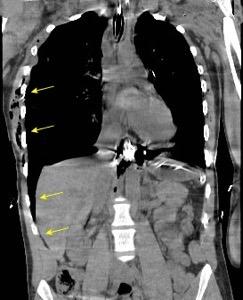

Signos radiológicos TC

Hallifax RJ et al. State-of-the-art: Radiological investigation of pleural disease Respiratory Medicine 2017

Nivel hidroaéreo o burbujas

Forma lenticular o elíptica Ángulos obtusos

> Grasa Extrapleural (60-80%)

Situación no gravitacional (no siempre)

Compresión de estructuras pulmonares

Límite muy bien definido Tabicación

Signo de la Pleura separada “Split pleural sign”

Capas pleurales de grosor uniforme realzadas por el contraste

No específico de empiema. Indica “exudado”. 68% de pacientes con empiema pleural.

Capas pleurales de grosor uniforme

Realce grasa extrapleural (30%)

> Grasa Extrapleural. (60-80%)

Kraus GJ. Split pleural sign. Radiology 2007